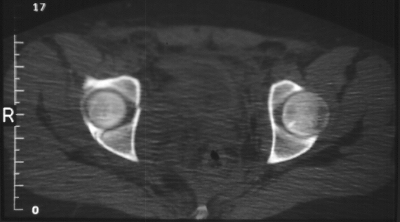

Radiographs:

Radiographs revealed a vertical buckle fracture of the right inferior sacrum, oblique fractures of the superior and inferior rami on the right and a fracture through the medial acetabulum. Obturator and iliac oblique inlet and outlet pelvic views, and a thin cut CT with 3-D reconstruction of the acetabulum were performed. These elucidated a comminuted anterior wall with fracture line extending to the posterior column. The posterior column was non-displaced. The pelvic fracture was non-displaced.

Assessment:

1. Right T-shaped acetabular fracture with anterior wall comminution.